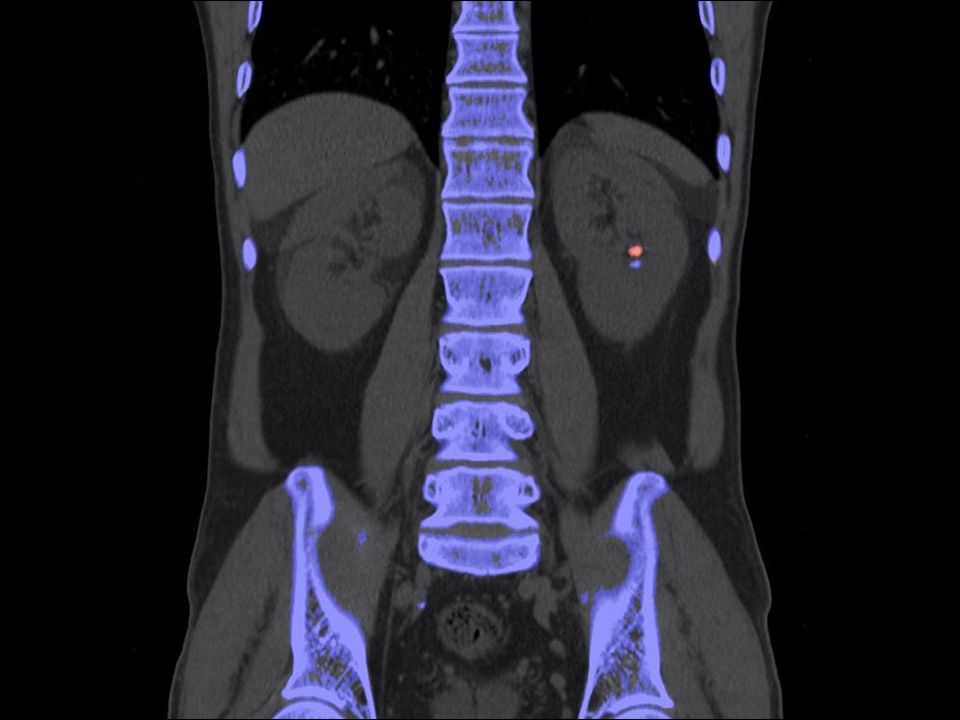

CT DE Calculi Characterization

Characterization of kidney stones.